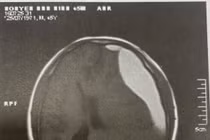

Người phụ nữ 37 tuổi chấn thương sọ não do cây đổ trong mưa bão

Bệnh viện Đa khoa tỉnh Cao Bằng đã tiếp nhận bệnh nhân chấn thương sọ não do cây đổ trong mưa bão.

Chấn thương sọ não kín không biểu hiện rõ ở giai đoạn đầu, nhưng lại tiềm ẩn nhiều nguy cơ nghiêm trọng. Phát hiện can thiệp sớm tránh các biến chứng nặng nề.